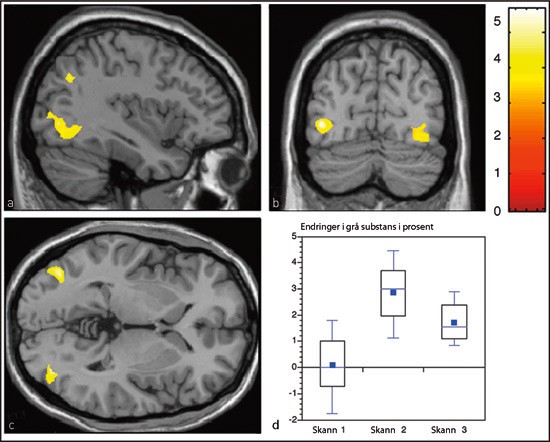

Den første prospektive studien om makrostrukturell sentralnervøs plastisitet hos mennesket ved læring ble publisert i Nature i 2004 (45). Friske, voksne mennesker, uerfarne som sjonglører, ble undersøkt med MR-basert morfometri. Halvparten øvde i inntil tre måneder på treballssjonglering, halvparten ikke. Når treningsgruppen hadde lært å sjonglere, ble de på nytt undersøkt med MR. Deretter avsluttet man treningen. En tredje cerebral MR ble utført tre måneder senere. Etter treningsperioden var det signifikant økt mengde grå substans midttemporalt bilateralt og i venstre sulcus intraparietalis i sjongleringsgruppen, som vist i figur 3 (45). Som eksempel var økningen i venstre midttemporalregion på om lag 3 %. Etter tre måneder uten sjonglering var økningen redusert til rundt det halve. På dette tidspunktet hadde de fleste i betydelig grad mistet evnen til å sjonglere. Dette indikerer en nær relasjon mellom sentralnervøs struktur og funksjon.